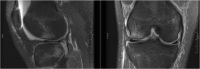

Recent findings: There has been interesting new research related to ACL reconstruction. As understanding of knee biomechanics following ACL injury and reconstruction has changed over time, many surgeons have changed their surgical techniques to low anterior drilling to position their femoral tunnel in an attempt to place the ACL in a more anatomic position. Even with this change in the femoral tunnel position, 85% of knees following ACL reconstruction have abnormal tibial motion compared to contralateral non-injured knees. Studies have shown increases in inflammatory cytokines in the knee following ACL injury, and newer MRI sequences have allowed for earlier objective detection of degenerative changes to cartilage following injury. Recent studies have shown that injecting IL-1 receptor antagonist and corticosteroids can modulate the post-injury inflammatory cascade. ACL reconstruction does not prevent the development of OA but can improve knee kinematics and reduce secondary injury to the cartilage and meniscus. Advancements in imaging studies has allowed for earlier detection of degenerative changes in the knee, which has allowed researchers to study how new interventions can alter the course of degenerative change in the knee following ACL injury.

Figures